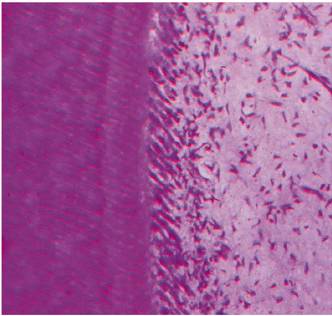

The histologic appearance of reparative dentin (Figure 19-30) demonstrates dentinal tubules that

are irregular, tortuous, or even absent. The increased thickness of the total

dentin is likely the reason for patients having decreased responses to cold

stimuli as time passes following a dental procedure. Quantitatively, it is

noted that the greater the degree of the "insult" caused by

preparations and restorative materials, the greater the amount of reparative

dentin that forms.

Although this calcified solid wall is considered beneficial and capable of

resisting further episodes of irritation, this healing phenomenon decreases the

ability of the tooth to respond to pulp testing at a later date.

Figure 19-30: Reparative dentin is deposited at specific sites as a result of injury (ie, caries, restorative procedures, attrition, or trauma).